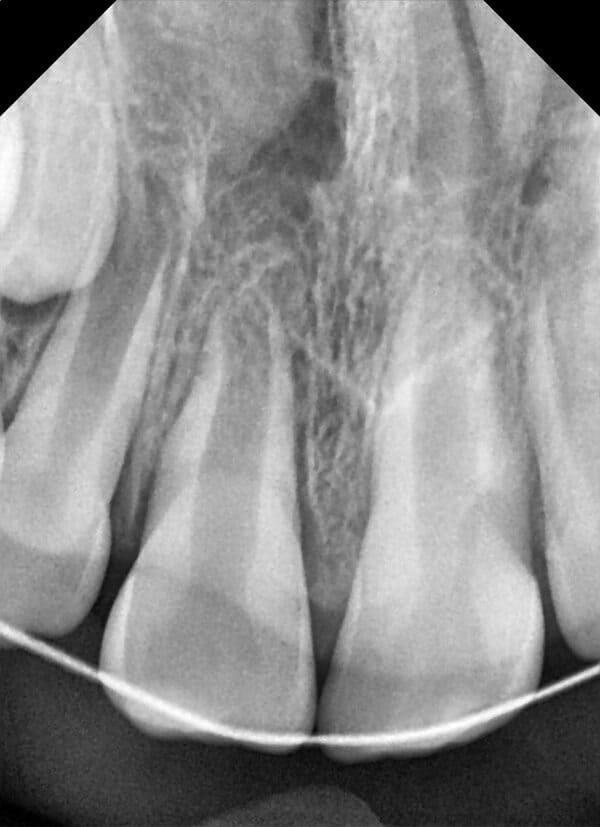

Дівчинка 7 років, перше вересня, гойдалка… Вивих постійного зуба: якщо в такій ситуації зволікати, дитина може втрати постійний зуб назавжди. Батькам порекомендували нас і пацієнти одразу приїхали. Через складність і травматичність процедур вирішено проводити лікування в анестезіологічному супроводі. Зуб поставлений на місце (репонований), проведена хірургічна обробка і ушивання рани губи. Останнє фото через рік після травми: зуб на місці і корінь продовжує розвиватись, губа повністю загоїлась